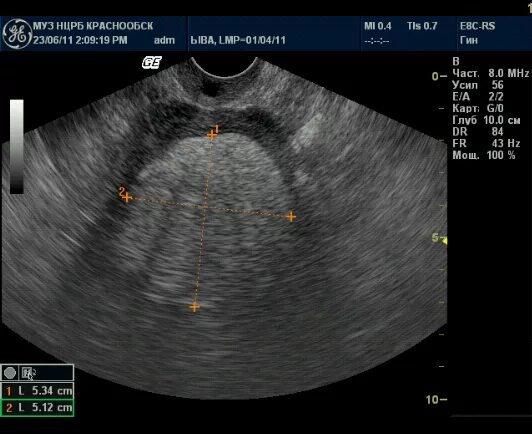

Включение в матке что это